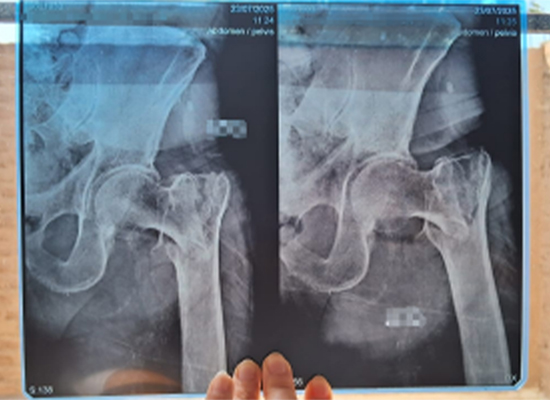

Las imágenes radiológicas confirmaron una fractura intertrocantérea izquierda desplazada , que requirió una intervención quirúrgica oportuna para restaurar la estabilidad y la movilidad.

Radiografía preoperatoria que muestra fractura intertrocantérea izquierda desplazada en paciente anciano, Lima Perú

Radiografía posoperatoria que muestra la fijación con clavo intramedular Intertan de una fractura intertrocantérea izquierda, Perú